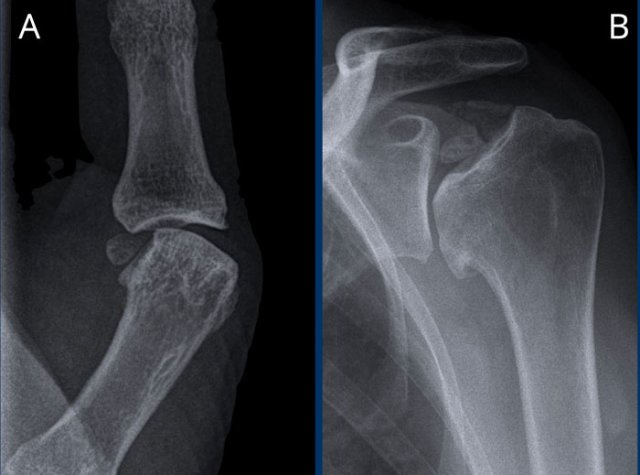

Images

A. Soft tissue calcifications in the rotator cuff. Patient got a subacromial injection for relief of symptoms.

B. After corticosteroid injection severe cartilage loss in the glenohumeral joint and bone destruction of the humeral head occured. This was the result of a septic arthritis, which is a rare complication of injection.